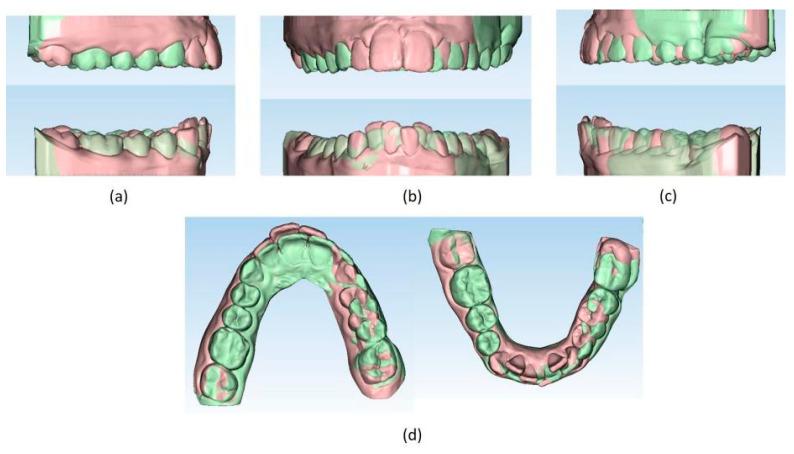

Successful closure of edentulous spaces with clear aligners (CAs) is influenced by many factors. CAs are tailored orthodontic devices whose predictability may have relevant medico-legal implications. This study presents a scoping review about missing molar space closure (MMSC) with CAs and a clinical case. This study aims to highlight the feasibility of molar space closure by mesialization with CAs without hybrid supports. Following PRISMA Sc-review guidelines, English-written randomized/non-randomized/observational clinical studies on PubMed, Scopus, Cochrane and Lilacs were searched. An 18-year-old patient, with upper and lower edentulous spaces due to the loss of two first molars, was rehabilitated with CAs (Sorridi, Sorridi srl, Latina, Italy) without hybrid supports and attachments. The therapy was carried out over 10 months. Currently, there are no studies documenting MMSC by mesialization with only CAs. Existing articles document the closure of premolar or incisor spaces. The upper and lower left second molars replaced the missing first molars, and erupting third molars replaced adjacent teeth. The biomechanical effects in space closure with CAs related to extraction cases appear as priorities of clinical/medico-legal interest. Our case turns attention to this movement of CAs without attachments/hybrid supports, indicating that even such a complex treatment can be comfortable for patients and safely predictable for specialists.

使用透明矫治器(CA)成功关闭无牙间隙受多种因素影响。CA是定制的正畸装置,其可预测性可能具有相关的医疗法律意义。本研究呈现了一项关于使用CA关闭缺失磨牙间隙(MMSC)的范围综述及一个临床病例。本研究旨在强调在无混合支持的情况下通过CA近中移动关闭磨牙间隙的可行性。遵循PRISMA范围综述指南,检索了PubMed、Scopus、Cochrane和Lilacs上英文撰写的随机/非随机/观察性临床研究。一名18岁患者因两颗第一磨牙缺失导致上下无牙间隙,使用CA(Sorridi,Sorridi srl,拉蒂纳,意大利)进行修复,无混合支持和附件。治疗持续了10个月。目前,尚无研究记录仅通过CA近中移动关闭MMSC的情况。现有文章记录了前磨牙或切牙间隙的关闭。上下颌左侧第二磨牙替代了缺失的第一磨牙,萌出的第三磨牙替代了相邻牙齿。与拔牙病例相关的CA关闭间隙的生物力学效应似乎是临床/医疗法律关注的重点。我们的病例将注意力转向了无附件/混合支持的CA这种移动方式,表明即使是如此复杂的治疗对患者来说也可以是舒适的,对专家来说也可以是安全可预测的。